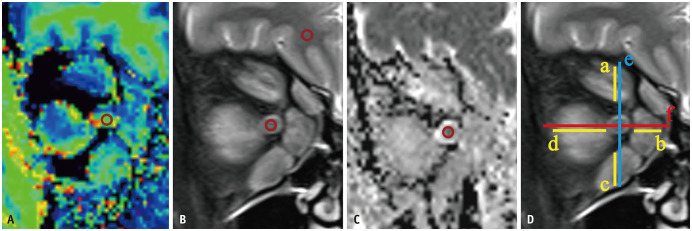

目的:评价磁化转移成像(MTI)对甲状腺功能障碍视神经病变(DON)的诊断价值,探讨MTI对常规t2加权成像(T2WI)和弥散加权成像(DWI)的附加价值。材料与方法:纳入149例甲状腺相关性眼病患者,分为训练组(有DON 46眼,无DON 148眼)和验证组(有DON 20眼,无DON 64眼)。眼眶磁共振成像(MRI)方案包括冠状面MTI、脂肪抑制T2WI和DWI。计算各组间各视神经磁化传递比(MTR)、信号强度比(SIR)、视神经表观扩散系数(ADC)及眼眶修正肌指数(mMI)的最小值、平均值和最大值,并进行比较。采用多变量logistic回归分析确定DON的独立影像学预测因素。采用二元logistic回归模型对各影像学预测指标及其组合诊断DON的表现进行评估,采用受试者工作特征(ROC)曲线分析。结果:DON组眼的MTRs和adc显著降低,SIRs显著升高,mMI显著升高。ON的MTRmean、ON的ADCmean和mMI是DON的独立预测因子。合并这三个变量的多变量模型的ROC曲线下面积(AUC)为0.946,在训练队列中,其诊断效能显著高于单独使用MTRmean (AUC = 0.831)、ADCmean (AUC = 0.738)或mMI (AUC = 0.862)(均P < 0.001)。在验证队列中,多变量模型取得了满意的诊断效果(AUC = 0.926)。结论:MTI可作为诊断DON的一种无创技术。在鉴别DON患者和非DON患者方面,MTR可以提供常规DWI的附加价值。

Materials and methods: One hundred and forty-nine patients with thyroid-associated ophthalmopathy were included and divided into training (46 eyes with DON and 148 eyes without DON) and validation (20 eyes with DON and 64 eyes without DON) cohorts. The orbital magnetic resonance imaging (MRI) protocols included coronal MTI, fat-suppressed T2WI, and DWI. The minimum, mean, and maximum values of the magnetization transfer ratio (MTR), signal intensity ratio (SIR), apparent diffusion coefficient (ADC) of each optic nerve (ON), and modified muscle index (mMI) of each orbit were calculated and compared between the groups. Multi-variable logistic regression analysis was performed to identify the independent imaging predictors of DON. The performance of each imaging predictor and their combinations using a binary logistic regression model for diagnosing DON was evaluated using receiver operating characteristic (ROC) curve analysis.